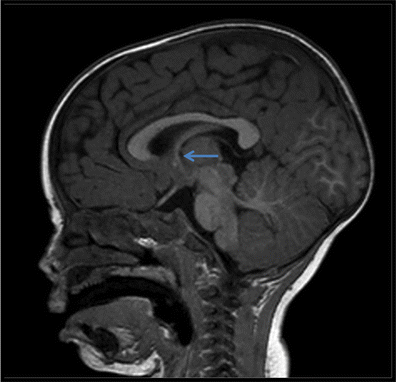

Midsagittal T1-weighted MRI of the brain noting the right foramen of Monro (arrow)